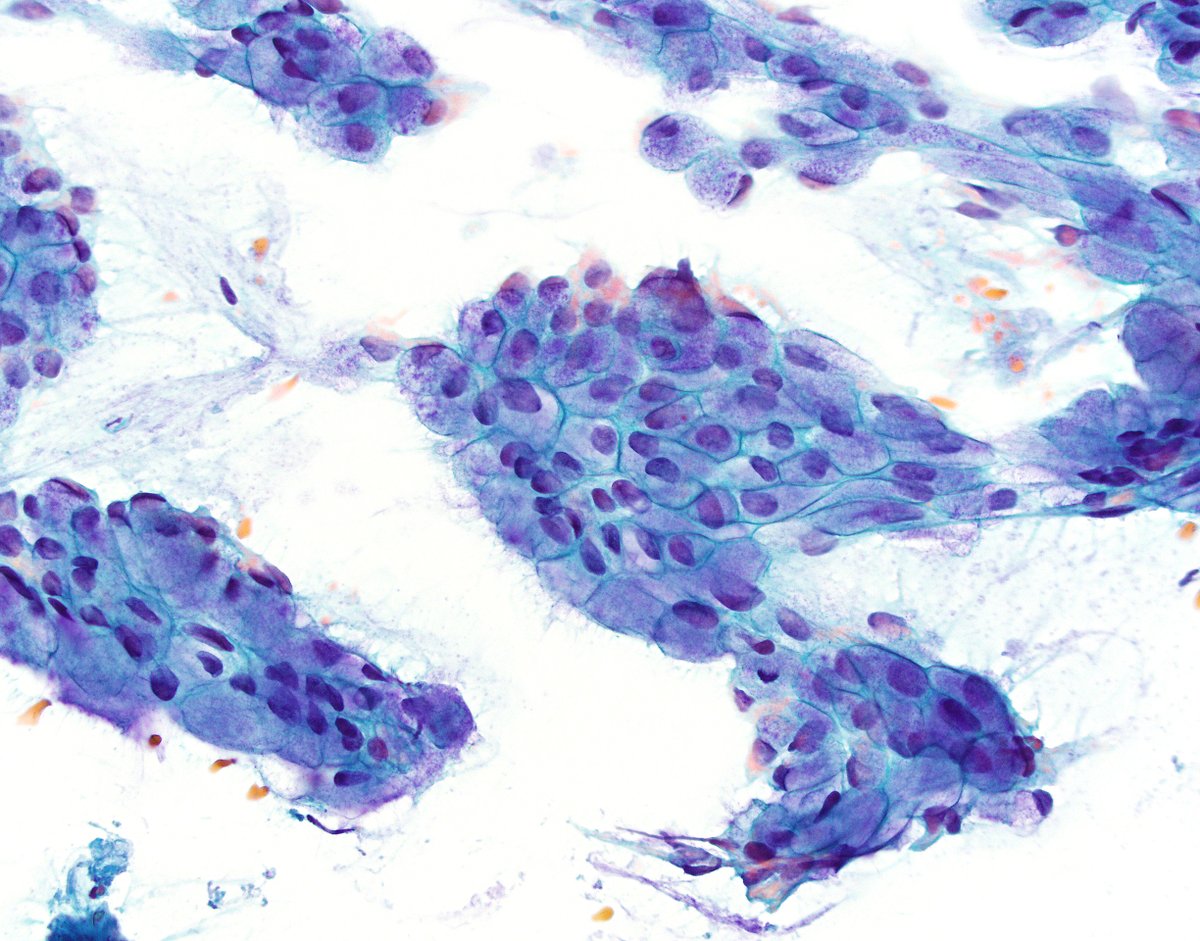

A teaching point from our Editors. How do you distinguish between intrapancreatic bile duct carcinoma and pancreatic ductal carcinoma? Samuel Freire